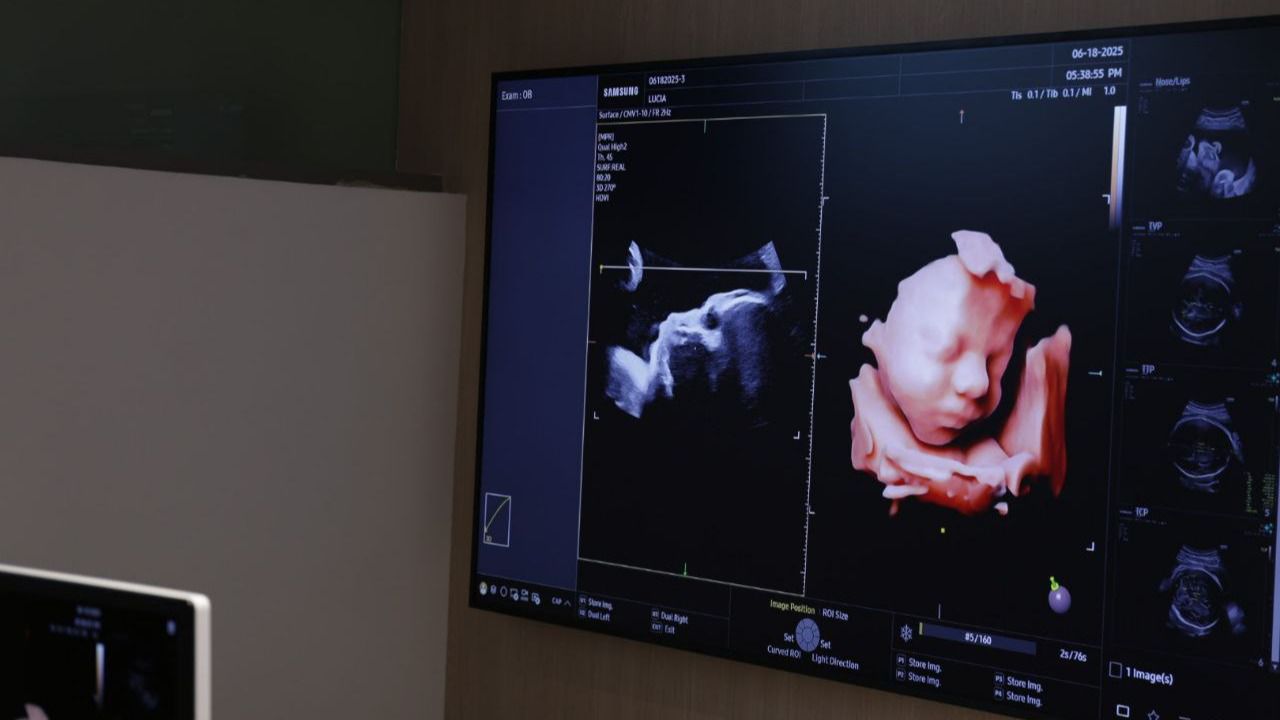

Uno de los momentos clave del evento fue la presentación en directo de los ecógrafos de última generación de Samsung, a cargo de la doctora María del Mar Gil, obstetra e investigadora en el Hospital Universitario de Torrejón y en el Hospital Universitario La Paz. La doctora mostró cómo la integración de IA en estos dispositivos está redefiniendo la exploración ginecológica.

“Estamos viviendo una auténtica revolución tecnológica en el ámbito clínico”, ha afirmado Gil. “Los nuevos sistemas de Samsung no solo permiten diagnósticos más rápidos, sino que ayudan al profesional en el proceso de aprendizaje, orientan en tiempo real y facilitan decisiones informadas con una fiabilidad extraordinaria”. Además, destacó el impacto directo en la relación con el paciente: “Al reducir los tiempos de exploración y aumentar la confianza diagnóstica, ganamos en cercanía, en empatía y en eficacia. Esto repercute en una atención más humana y personalizada”.